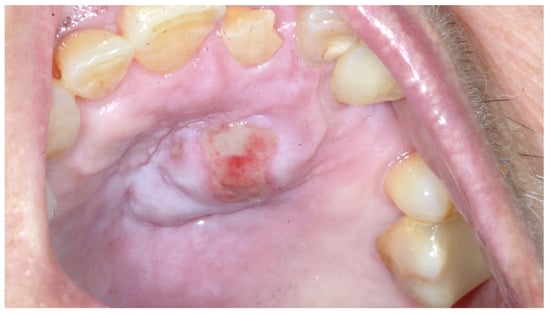

3. Case Presentation